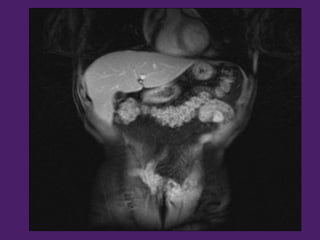

Bazo

Estómago

Pedículo

esplénico

Riñón izquierdo

Riñón

izquierdo

BazoCuerpo del

Páncreas

Arteria esplénica

Colon

Transverso